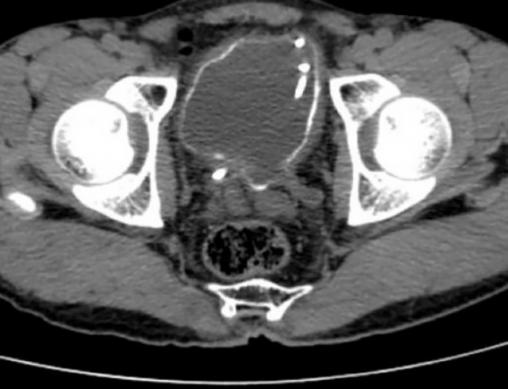

Les symptômes persistant, un scanner pelvien, quelques jours après, révèle une importante calcification de la paroi vésicale (figure).

L’ASP peut objectiver des calcifications de la paroi vésicale, et de l’uretère. À l’échographie ou au scanner pelvien : calcifications, pseudopolypes vésicaux, résidu post-mictionnel, mais aussi urétéro-hydronéphroses, dilatations pyélocalicielles avec image en boule.